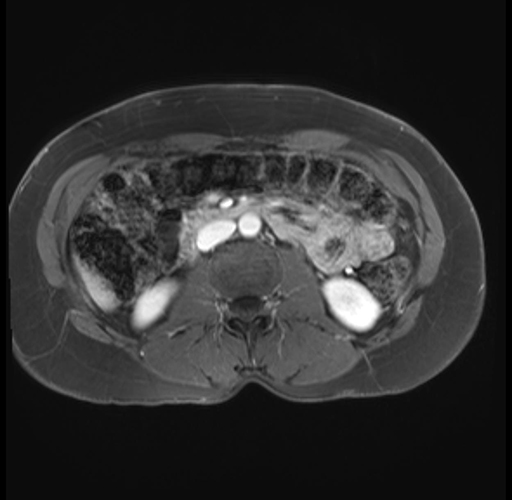

Imaging Analysis

Look through the patient's CT scan to identify any areas of concern for the necessary procedure.

Based on your CT findings, which issue(s) are present and would give reason for "planned slowing down moment(s)" in this case?